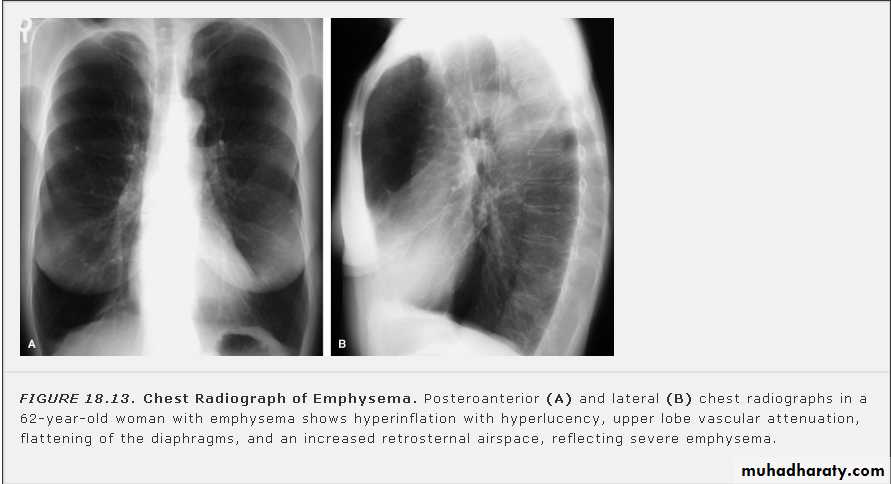

عرض